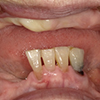

4.支座的连结

作为人工牙齿的支座的植入部分(abutment)与固定物连接。